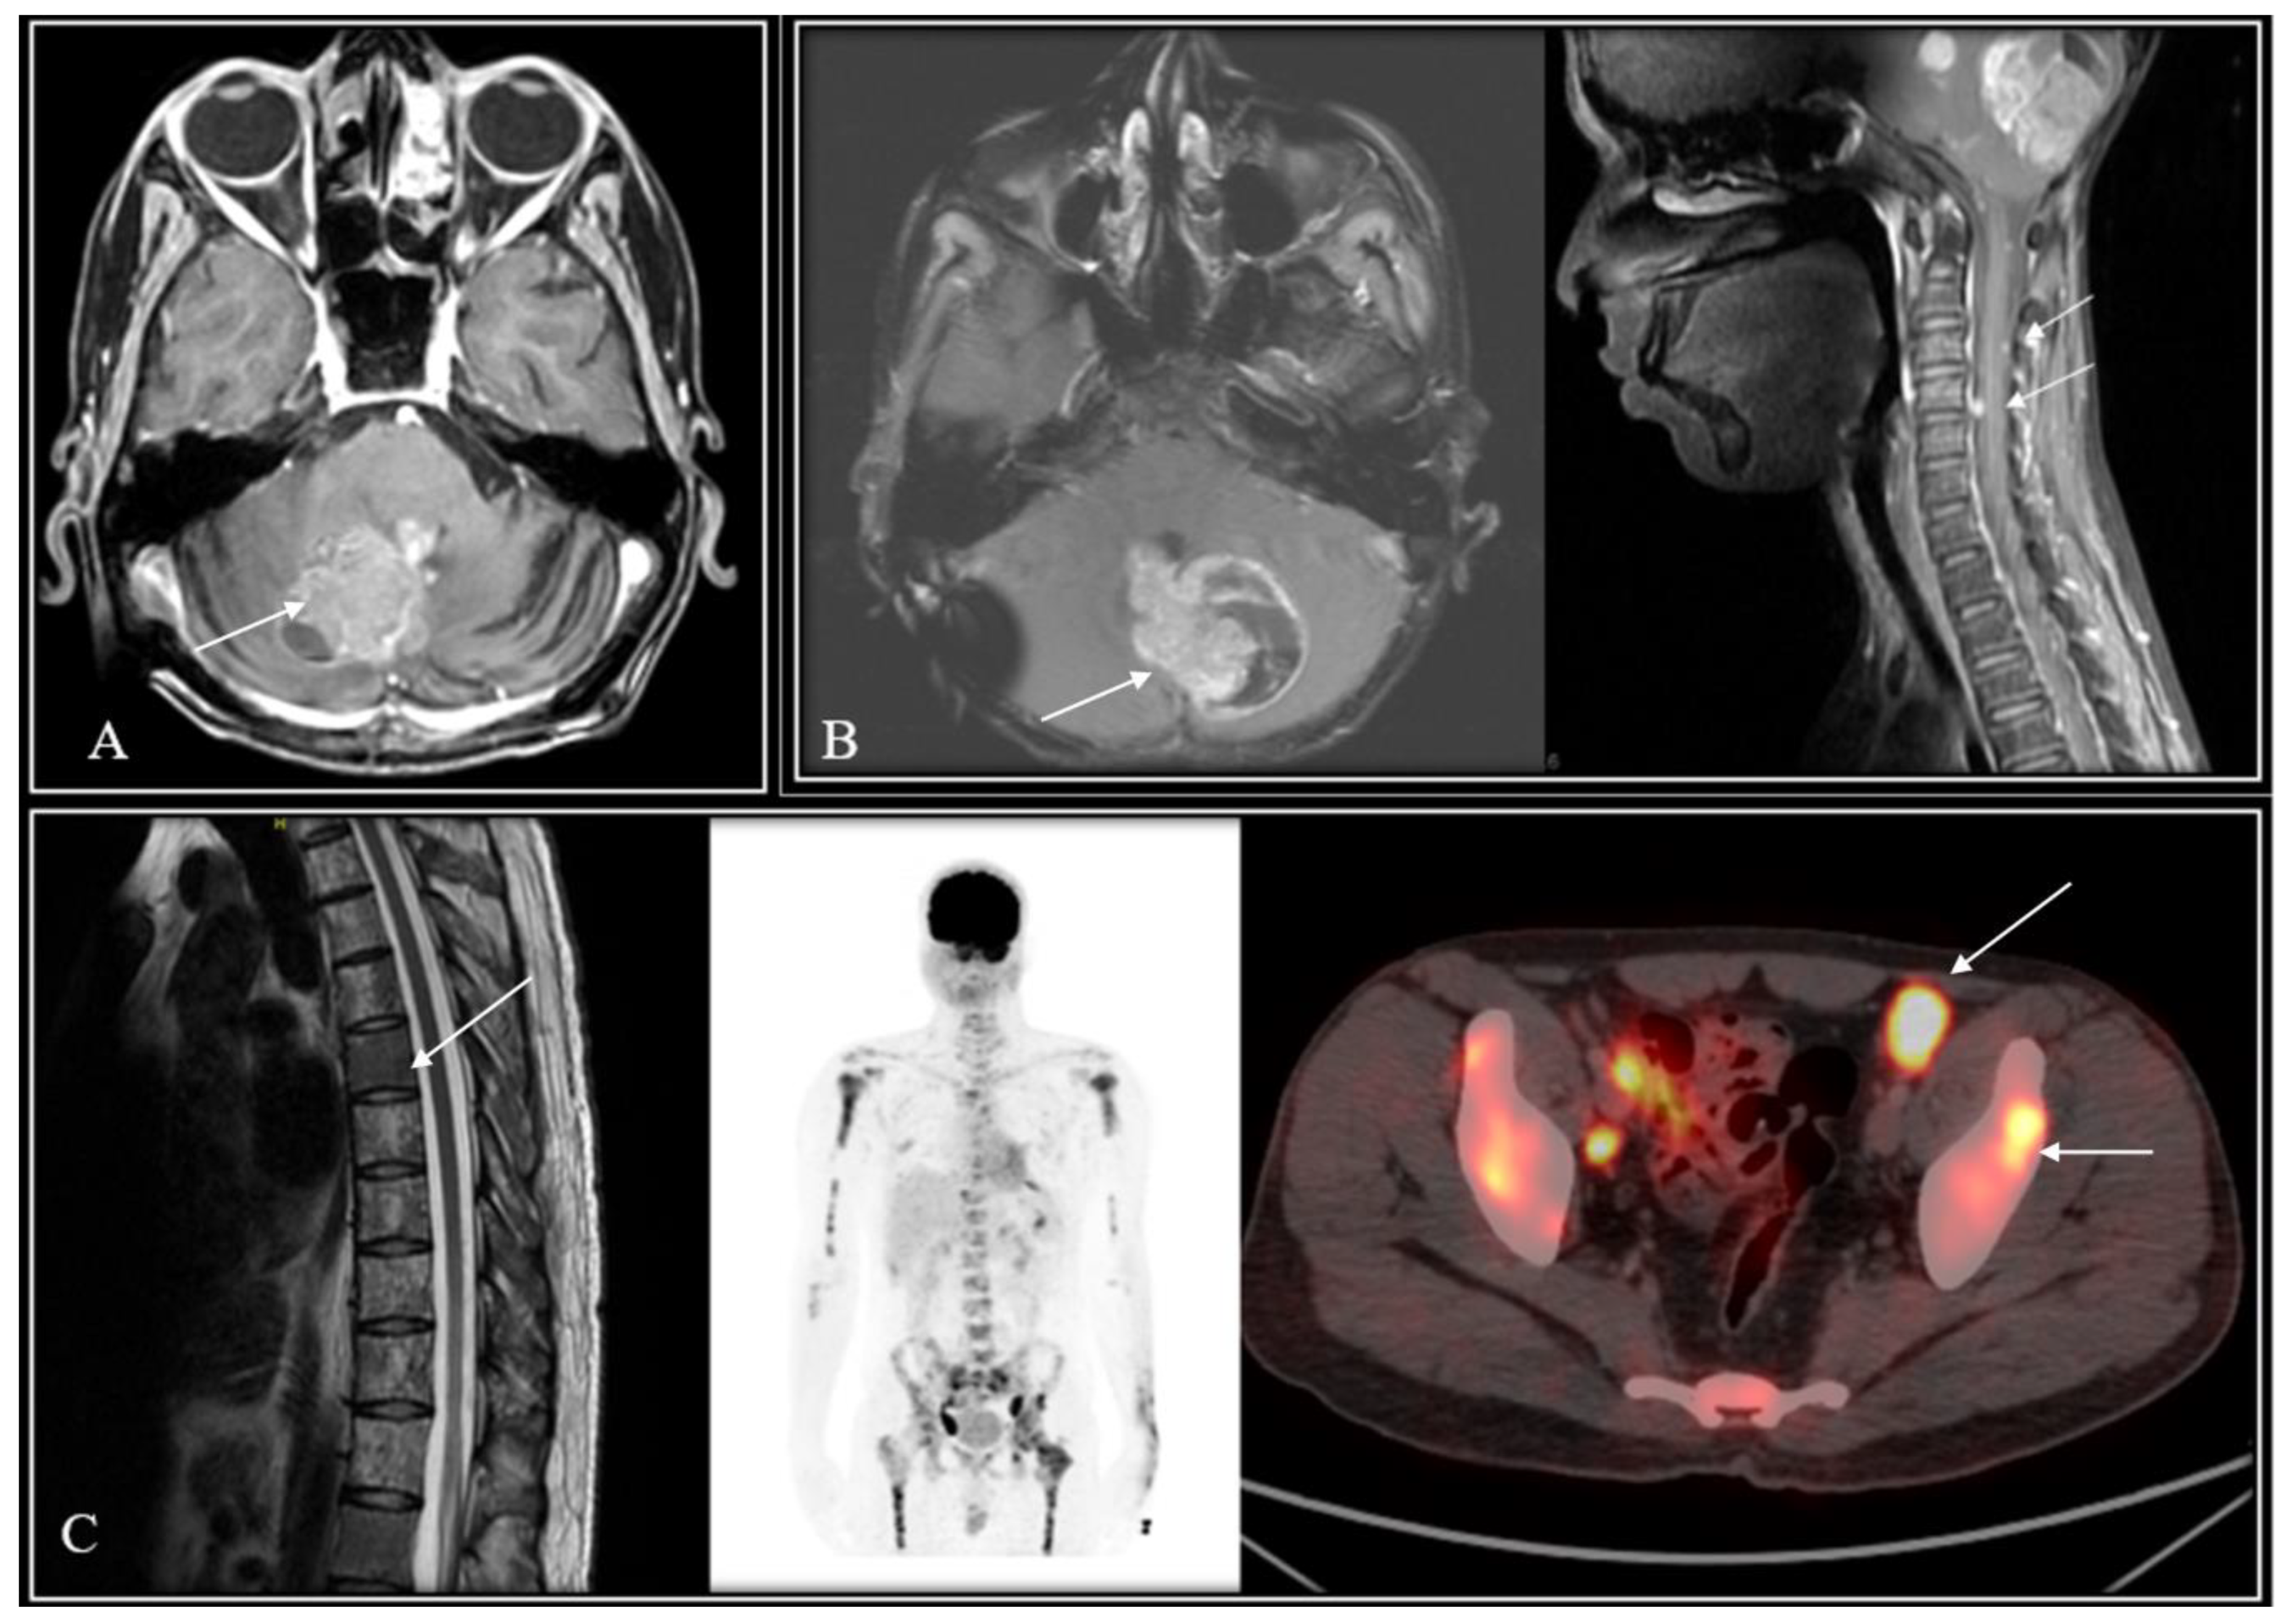

| W1 | 9/Male | Nonmetastatic | 36 Gy/18 fx | Tumour-bed recurrence | 25 months | Re-RT and chemotherapy | Died of disease | 80 months |

| W2 | 11/Male | Nonmetastatic | 26 Gy/13 fx | Tumour-bed relapse plus metastases in brainstem, temporal lobe, and spine | 37 months | Re-CSI (36 Gy/36fx) and chemotherapy | Died of disease | 66 months |

| W3 | 13/Female | Nonmetastatic | 35 Gy/21 fx | Leptomeningeal dissemination | 25 months | Best supportive care | Died of disease | 25 months |

| W4 | 10/Male | Nonmetastatic | 14.4 Gy/8 fx (Incomplete RT) | Leptomeningeal dissemination | 61 months | Best supportive care | Died of disease | 62 months |

| W5 | 27/Male | Nonmetastatic | 35 Gy/21 fx | Leptomeningeal dissemination | 58 months | Best supportive care | Died of disease | 60 months |

| W6 | 14/Male | Metastatic (frontal horn lesion) | 35 Gy/21 fx | No evidence of disease progression/failure | 15 months | Not applicable | Died of toxicity | 15 months |

| W7 | 9/Male | Nonmetastatic | 36 Gy/18 fx | Tumour-bed recurrence | 56 months | Resurgery | Died of disease | 60 months |

| W8 | 22/Male | Nonmetastatic | 35 Gy/21 fx | Extra-neural metastases | 83 months | Chemotherapy | Alive with disease | Not applicable |

| W9 | 15/Male | Nonmetastatic | Not known | Tumour-bed relapse plus metastases in frontal horn and multiple spinal metastases | 59 months | Resurgery | Died of disease | 67 months |